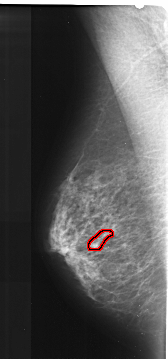

FILE: A_1032_1.LEFT_CC.OVERLAY

TOTAL_ABNORMALITIES 1

ABNORMALITY 1

LESION_TYPE CALCIFICATION TYPE FINE_LINEAR_BRANCHING DISTRIBUTION LINEAR

ASSESSMENT 4

SUBTLETY 3

PATHOLOGY MALIGNANT

TOTAL_OUTLINES 1

BOUNDARY